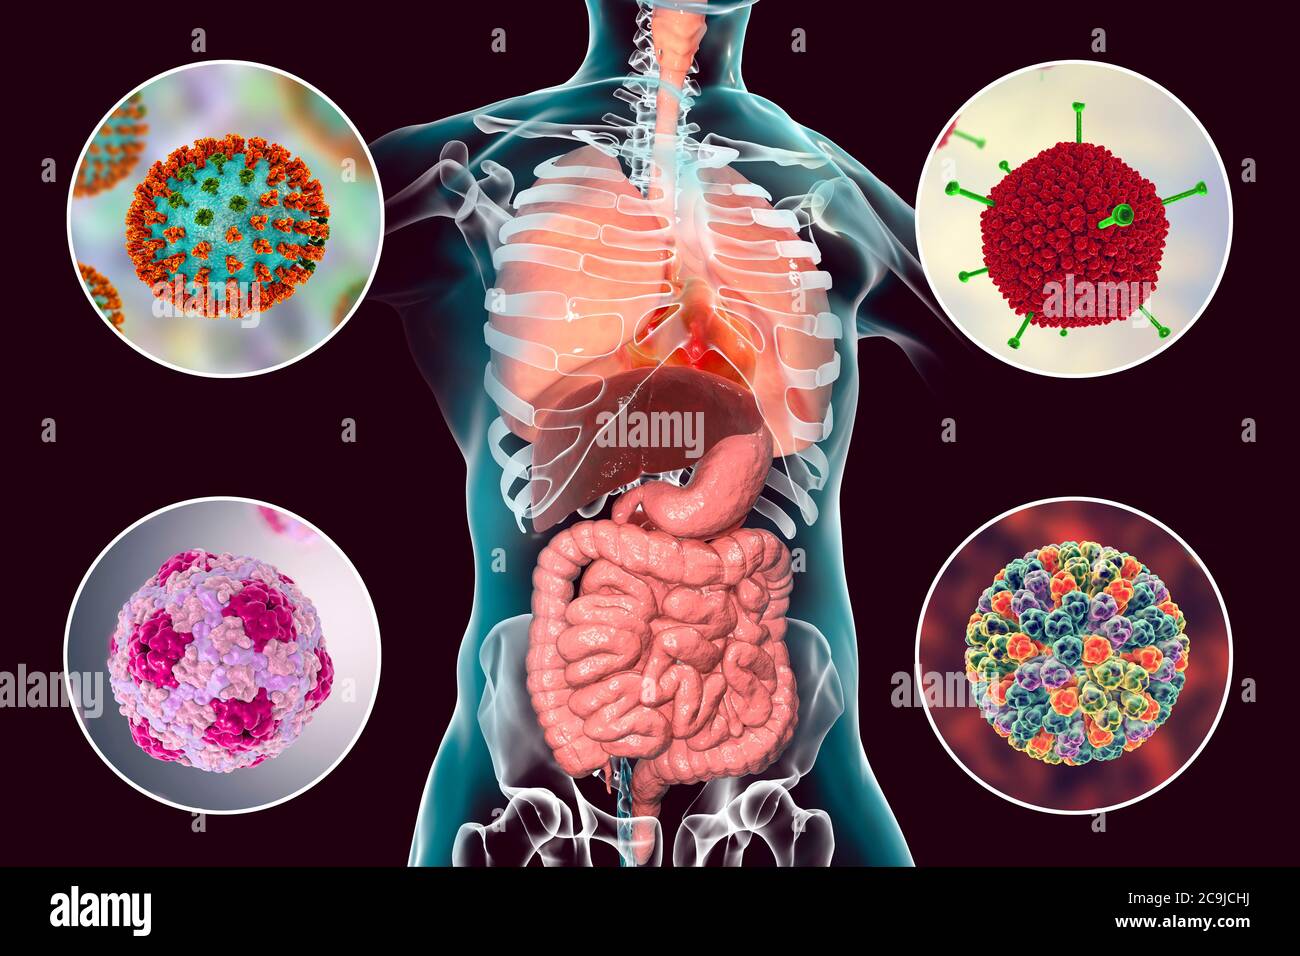

Revue générale des infections virales respiratoires – L’étiologie, la physiopathologie, les symptômes, les signes, les diagnostics et les pronostics à partir des Manuels MSD,.

De nombreux agents pathogènes peuvent provoquer des infections des voies respiratoires. Bon nombre de ces infections produisent des signes et des symptômes similaires, mais.

Selon l'Organisation mondiale de la santé, les infections des voies respiratoires telles que la tuberculose, la grippe et la pneumonie ont été responsables de plus de 4 millions de.